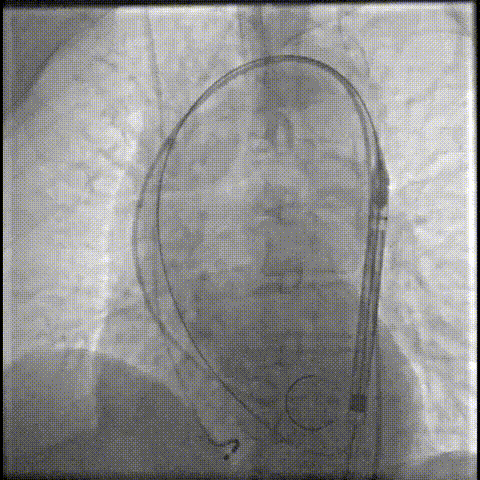

主动脉根部造影